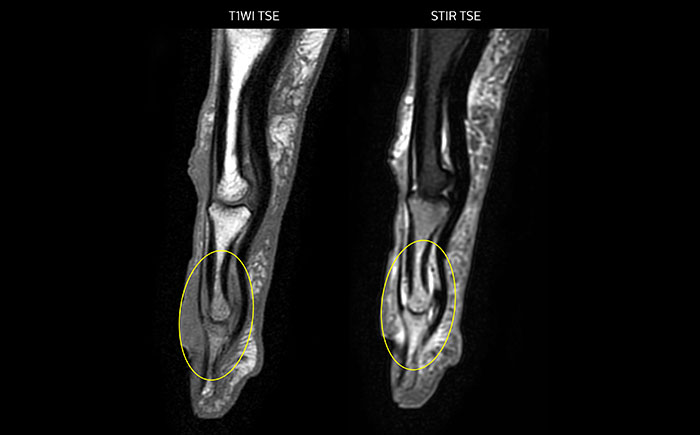

mDIXON TSE of ankle

MRI examination on Prodiva 1.5T of a 72-year-old female with a malignant melanoma in the ankle. mDIXON TSE provides excellent fat

suppression, without the distortion that is often seen at such extremities.

mDIXON TSE of ankle melanoma